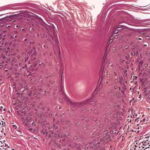

Pathologic findings in pityriasis rubra pilaris vary according to the duration of the disease. The findings are most likely to be diagnostic in the acute phase, when hyperkeratosis, acanthosis with broad short rete ridges, and alternating orthokeratosis and parakeratosis oriented in both horizontal and vertical directions can be observed (see Pityriasis Rubra Pilaris At a Glance). Usually, there is a sparse superficial, perivascular lymphocytic infiltrate in the underlying dermis. Keratinous plugs of the follicular infundibula as well as perifollicular areas of parakeratosis may also be present. A prominent granular layer and dilated, but not tortuous, capillaries are features that help to distinguish pityriasis rubra pilaris from psoriasis, the most important differential diagnosis.